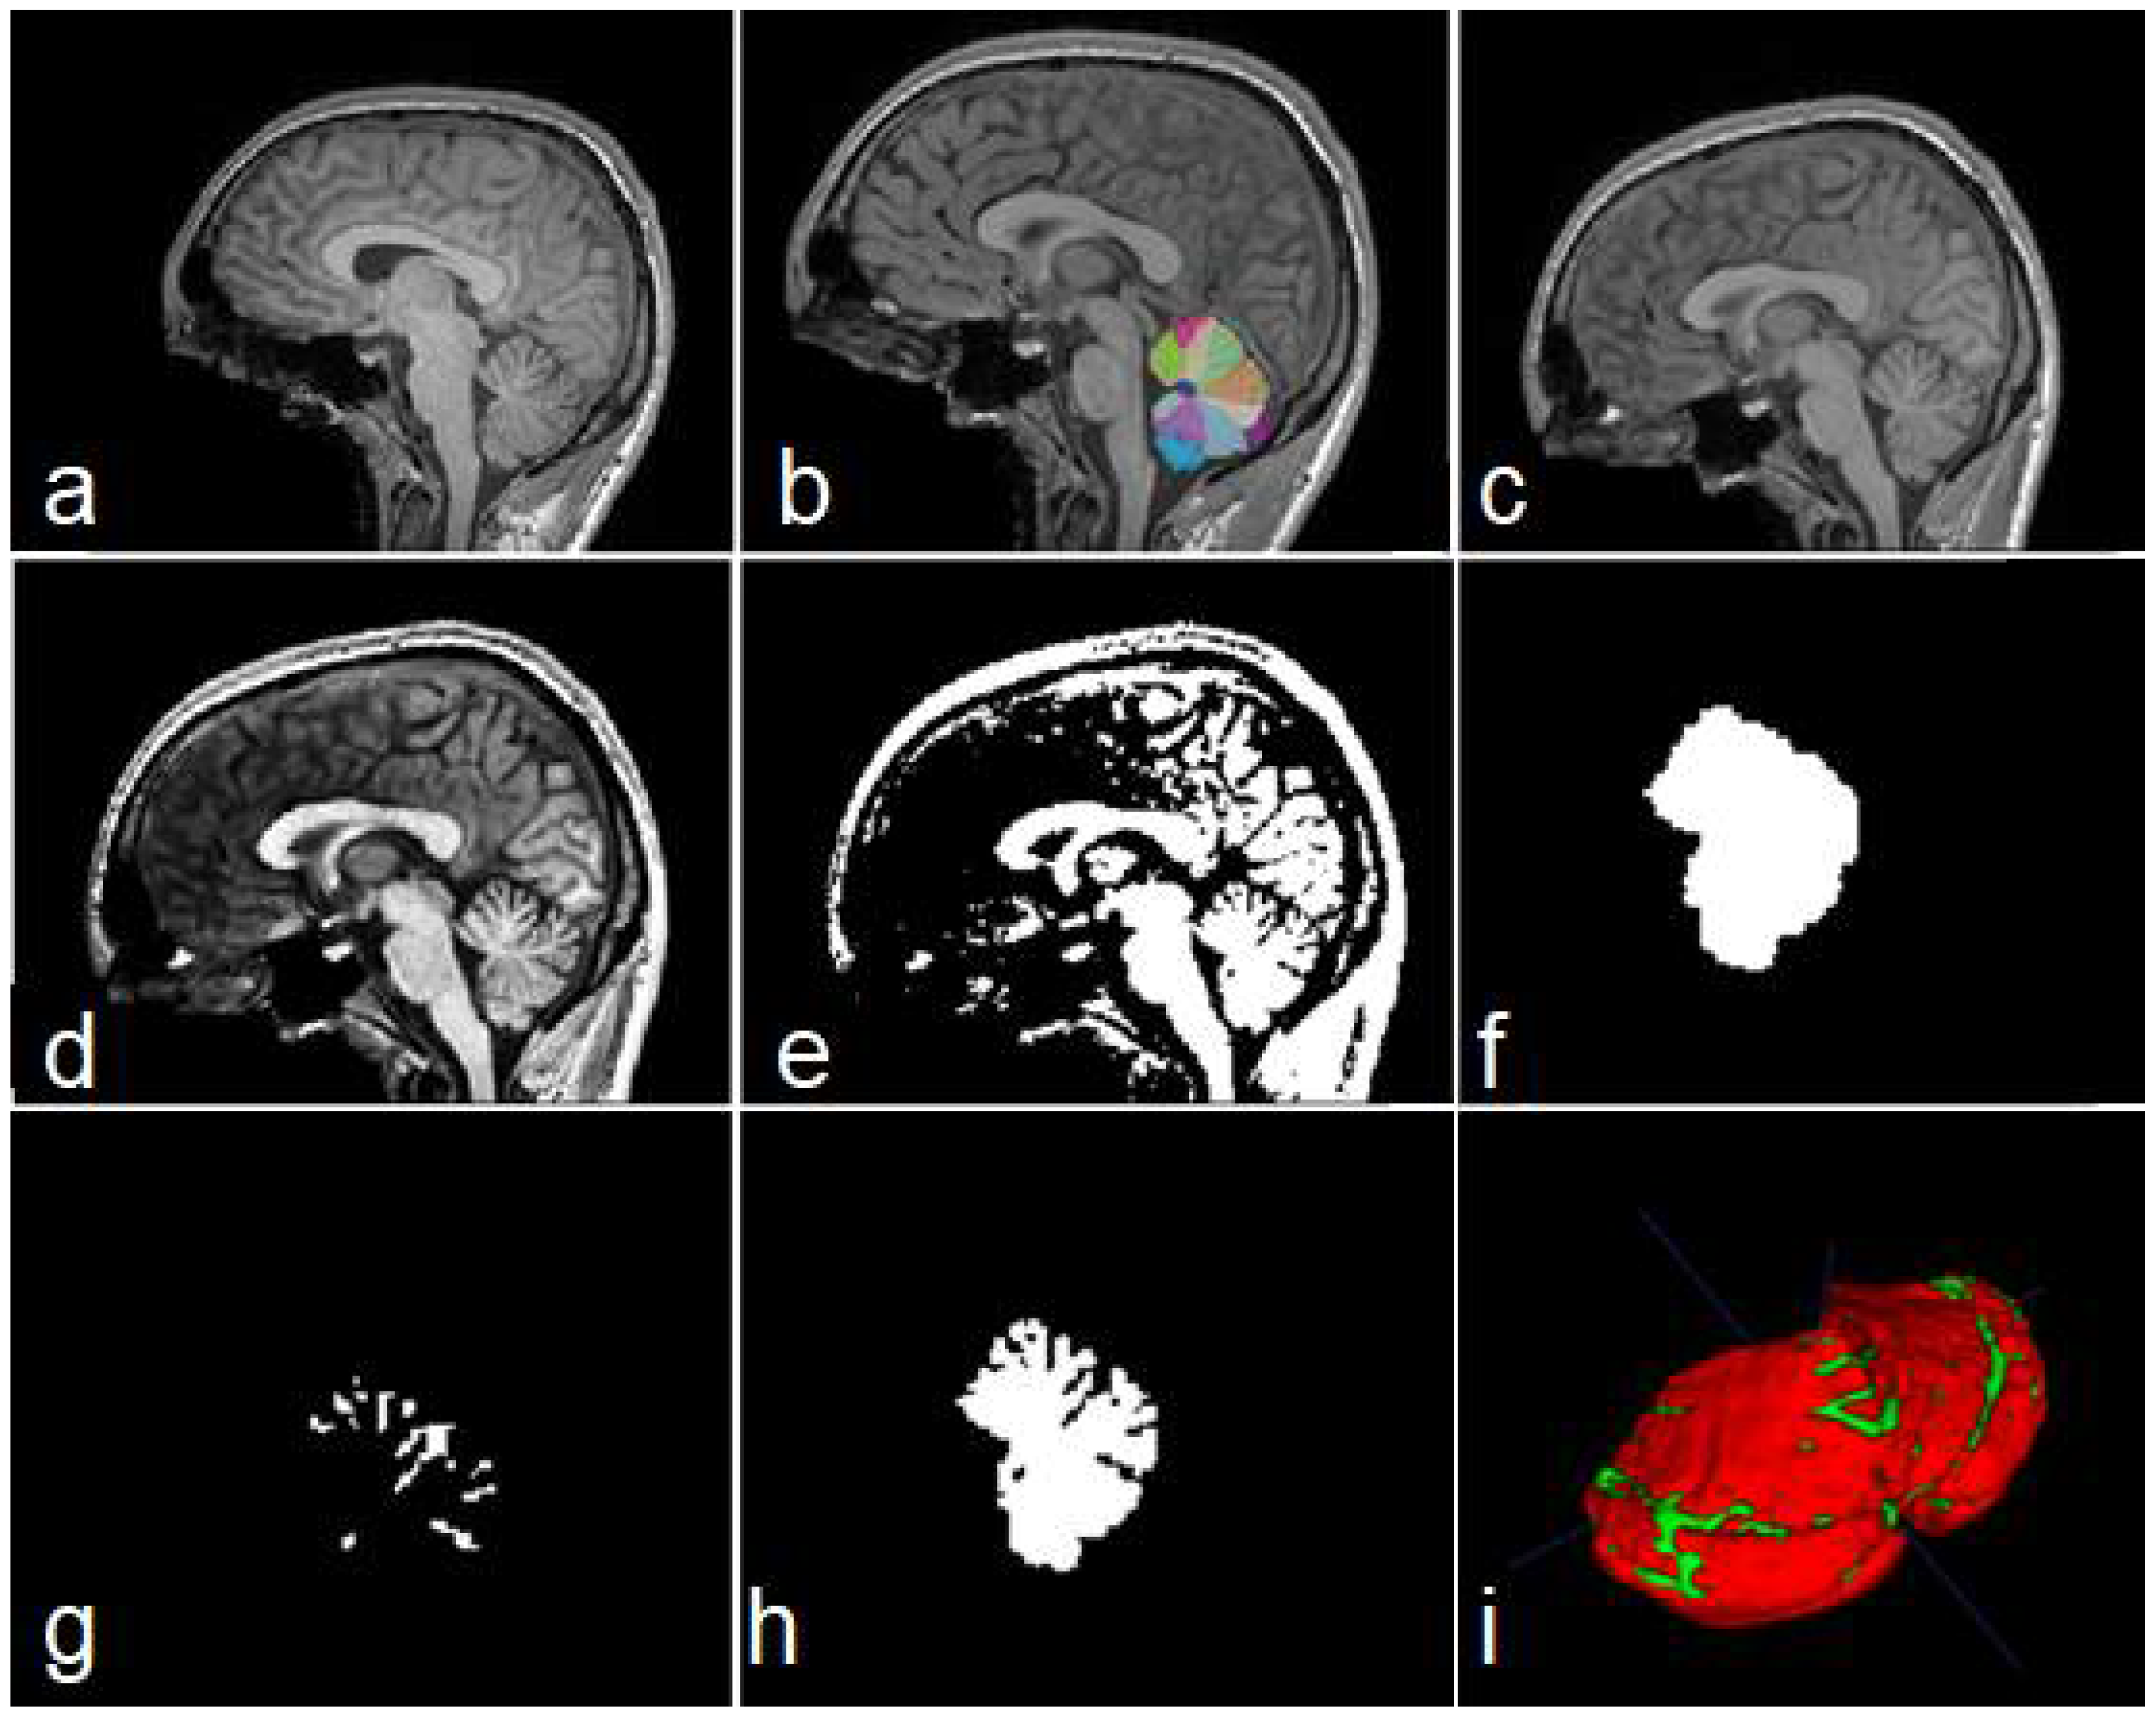

Building a manually labelled dataset from 3D images is a very difficult task. For this reason, we created a simple procedure for the preparation of our dataset. For each MRI, the following steps were applied:

• Obtain a cerebellar mask, using any existent technique. See Figure 3b.

• Bias Field Correction (BFC) for reducing intensity inhomogeneities. The algorithm used in this research was the N4 method [32].

• Image registration to the 1 mm isotropic ICBM 2009c template [33] in MNI space. See Figure 3c.

• Obtain a contrast-enhanced image (Figure 3d).

• Binarize equalized image using any existent technique (Figure 3e).

• Build a mask containing the cerebellar segmentation obtained in step 1 (output 1). See Figure 3f.

• Build a feature map containing cerebellar fissures, by applying binary xor operation to outputs from steps 5 and 6 (output 2, Figure 3g,i).

• Build a feature map containing the cerebellar tissue, with all its fissures, by subtracting output 1 from output 2 (output 3, Figure 3h,i).

• Imaging cropping for reducing computational cost.

Figure 3. Steps of data construction procedure. Sagittal views of the original image (a), cerebellar mask obtained with ACAPULCO (b), result of BFC and registration (c), contrast-enhanced image (d), binary image obtained (e), feature map containing the whole cerebellar tissue (f), obtained fissures mask (g), and cerebellum with fissures (h). In (i) a 3D view of the union of (g,h); red color represents the cerebellar tissue, and green color shows the fissures.